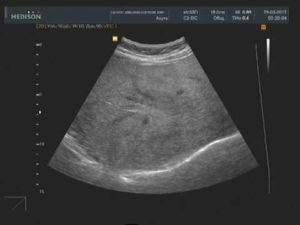

Диагноз в случае стеатоза ставится на основе инструментальных методов исследования — УЗИ печени, биохимического анализа крови. На УЗИ печень имеет «пестрый» вид за счет неравномерной структуры заполненных жирами гепатоцитов, а в анализах крови повышаются печеночные ферменты (АСАТ, АЛАТ), а также липиды крови, что отражает тесную связь между нарушением липидного обмена и стеатозом.

УЗИ печени позволяет выявить морфологические и структурные изменения органа, такие как:

- Гиперэхогенность – уплотнение тканей.

- Гепатомегалию – увеличение размеров печени.

- Жировую инфильтрацию – скопление веществ, которые в норме отсутствуют.

- Неоднородность плотности органа.

Признаки жирового гепатоза на УЗИ

При УЗИ могут быть выявлены следующие эхопризнаки гепатоза:

- уплотнение тканей печени

- увеличение размеров органа и его выход за края подреберной области

- жировое перерождение тканей печени

- неоднородность распространения поврежденных участков по органу.

УЗИ-признаки жирового гепатоза печени

Выделяют диффузную, локальную, очаговую и периферическую формы жировой инфильтрации, которые отличаются лишь распространением поражения. При диффузной форме размеры печени умеренно увеличиваются, но форма при этом не меняется.

Ультразвуковое исследование показывает снижение звукопроводимости органа, которое проявляется неотчетливой визуализацией глубоких отделов печени и диафрагмы и ухудшением визуализации мелких ветвей венозного рисунка.

- Диффузную. Степень характеризуется тотальным и равномерным распределением жировой ткани по всей печени. Врачи-сонологи подобное поражение органа выносят в заключение как – диффузные изменения в печени по типу жировой инфильтрации (как на фото).